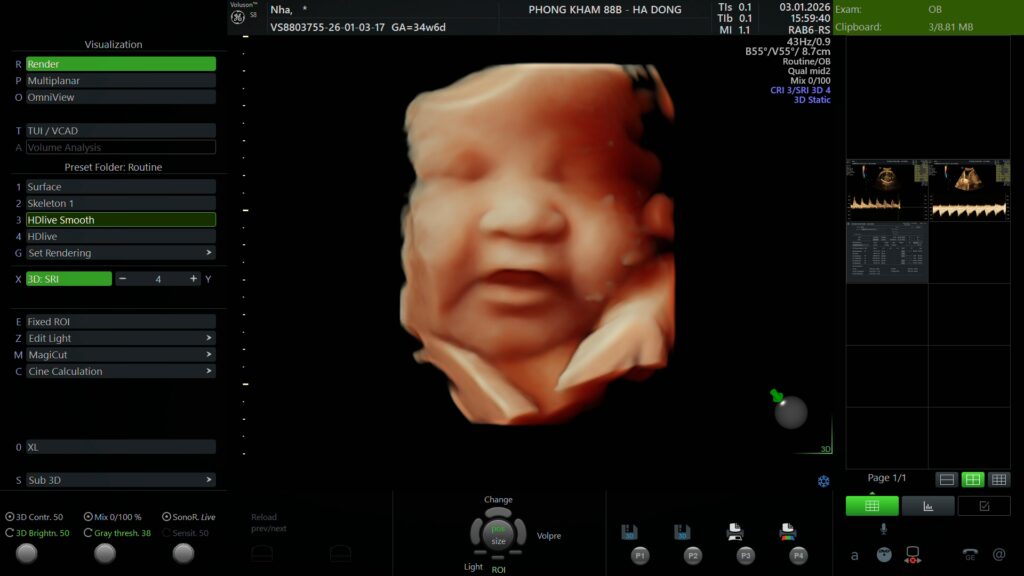

Phòng khám Sản phụ khoa 88B chúc mừng mẹ Ngô Thị Thanh Nhã đã hoàn thành buổi thăm khám và siêu âm định kỳ vào ngày 3/1/2026.

Dưới đây là hồ sơ kết quả siêu âm chi tiết được thực hiện và trực tiếp phân tích bởi Bác sĩ Nguyễn Dương Diệp

Phiếu kết quả siêu âm

(Mẹ vui lòng xem chi tiết các chỉ số sinh học và đánh giá hình thái thai nhi trong ảnh dưới đây)

Các chỉ số của bé hiện tại đang phát triển tương ứng với tuổi thai.